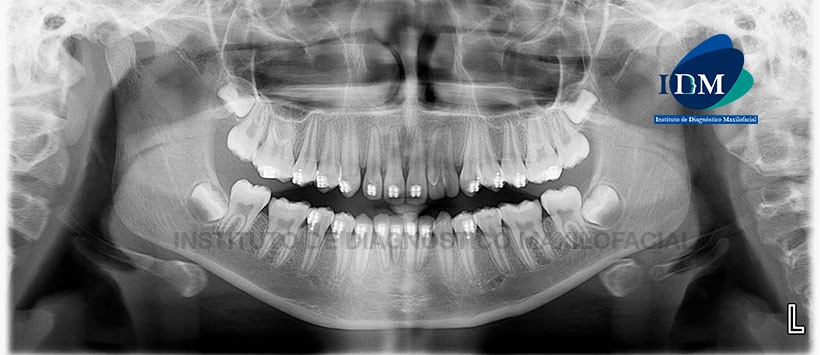

Paciente femenino de 11 años de edad, es referido al Instituto de Diagnóstico Maxilofacial – IDM (Sede Surco) para evaluación tomográfica de pieza supernumeraria.

En la radiografía panorámica (Figura 1) se observa pieza supernumeraria localizada entre piezas 2.2 y 2.3, en aparente fusión con la pieza 2.2.

A la evaluación de la tomografía volumétrica (CBCT) en los cortes axiales (Figura 2), transaxiales (Figura 3) y tangenciales (Figura 4), se confirma la fusión dentaria incompleta da nivel del tercio cervical hacia el tercio apical radicular de la pieza 2.2 con pieza supernumeraria adyacente por distal. Se observa coronas, cámaras pulpares, conductos radiculares y ápices independientes. Se evidencia presencia de cúspide en talón de pieza 2.2 y características morfológicas de pieza supernumeraria semejante a pieza 2.2

Conclusión: Fusión dentaria incompleta de pieza 2.2 con pieza suplementaria.